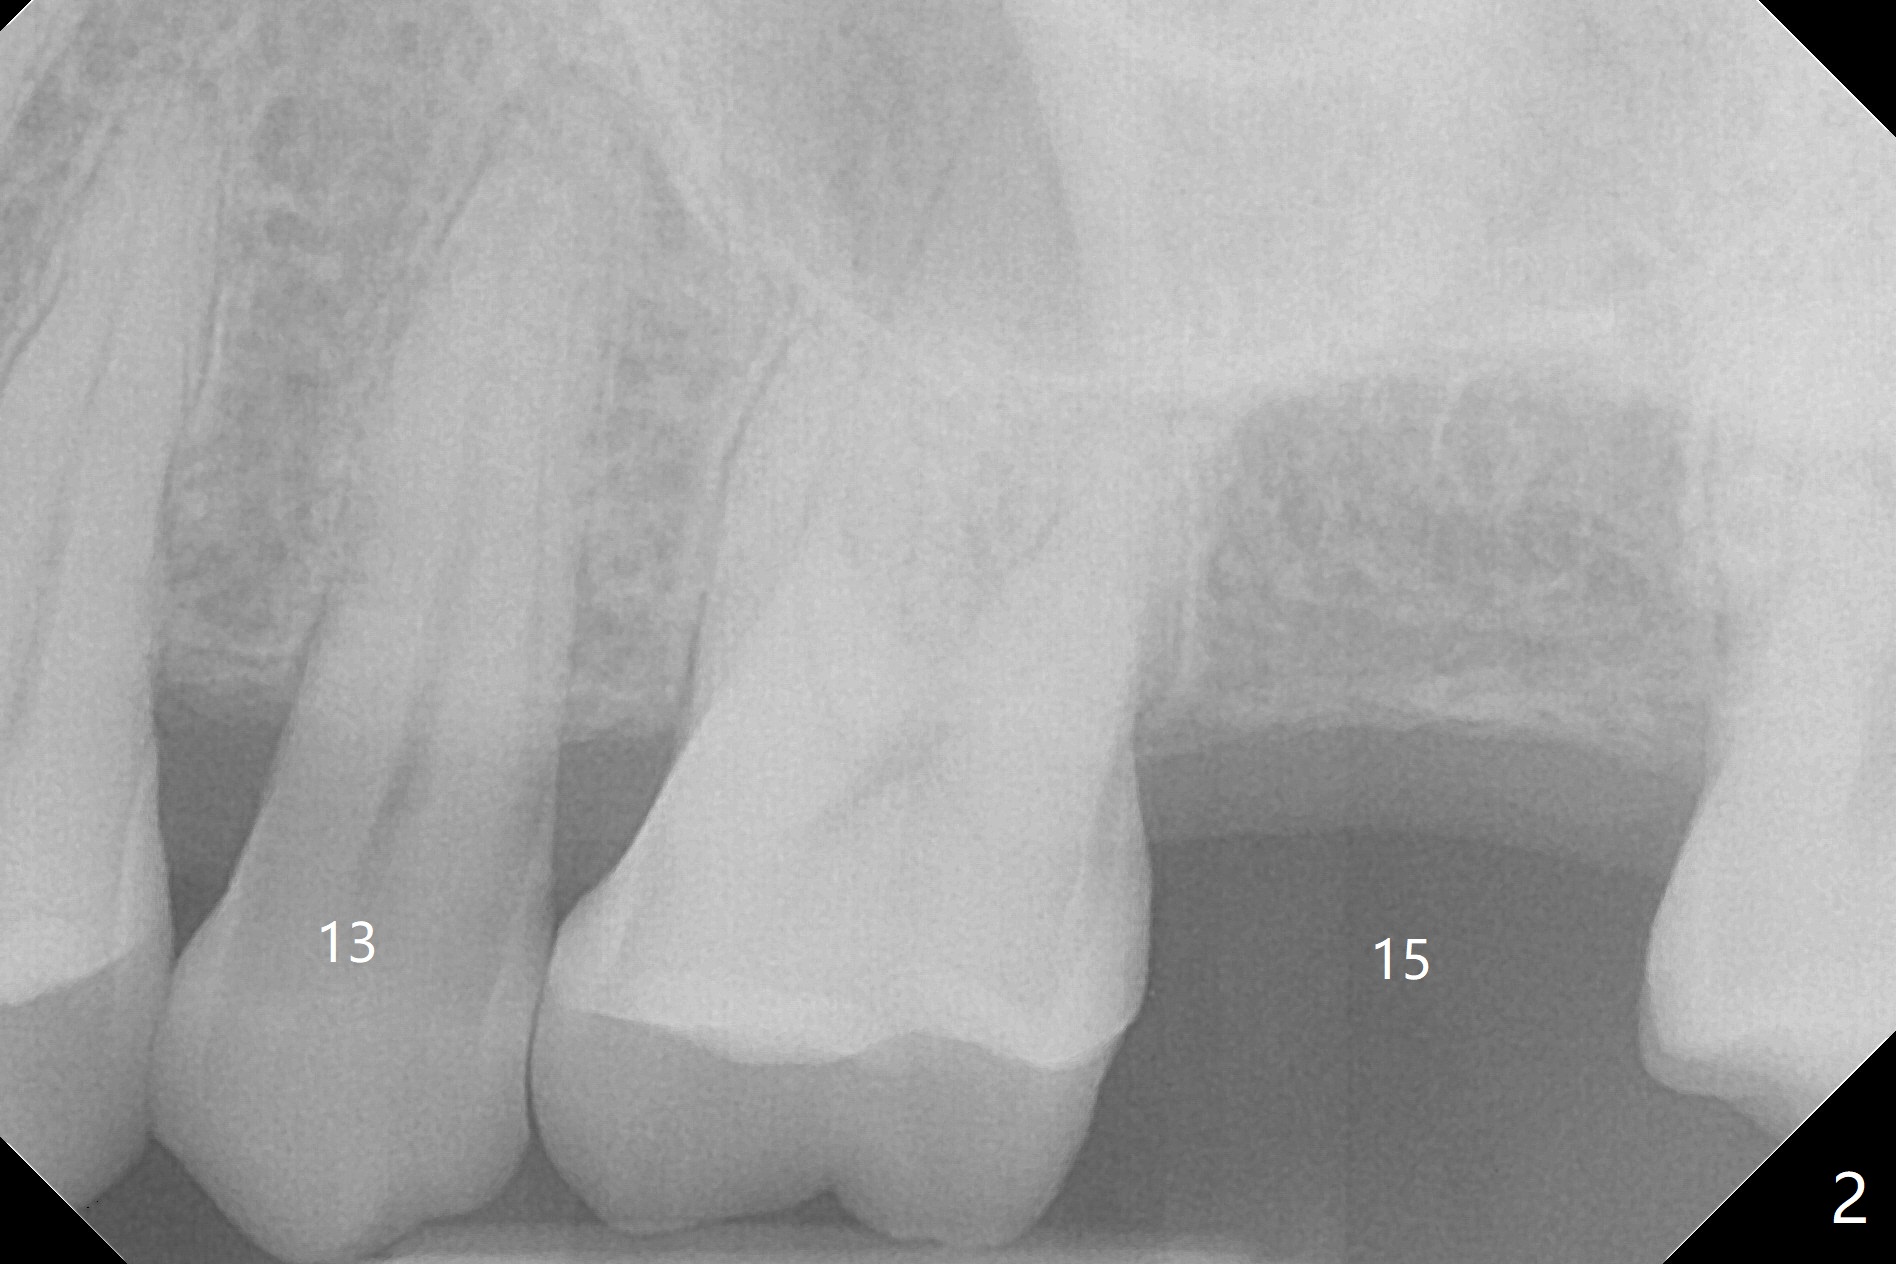

A 65-year-old man cracks 3 teeth in ~2 years (Fig.1,2 (#4,13,15)). The tooth #4 is symptomatic after RCT (Fig.1); it appears that the buccal canal is incompletely filled (data not shown). In fact an exam 1 month later shows that the symptomatic tooth is #2 (crack), while #4 is salvageable (Fig.8). The tooth #13 has palatal subgingival fracture with severe pain (Fig.2 with palatal defect). In fact the title of this case is incorrect). After extraction, allograft is placed (Fig.3 *) with 6-month membrane. In fact the bone graft is not packed into the apex of the socket; a condenser should have been used. The patient returns 3 days postop before leaving abroad. The 6-month membrane remains in place (Fig.4), while the ridge at #15 is minimally atrophic (Fig.5). The coronal lamina dura becomes indistinct 5 months postop (Fig.6). The bone graft remains in the socket. The distoapical portion of a 4x11.5 mm implant may be in the sinus (Fig.7).